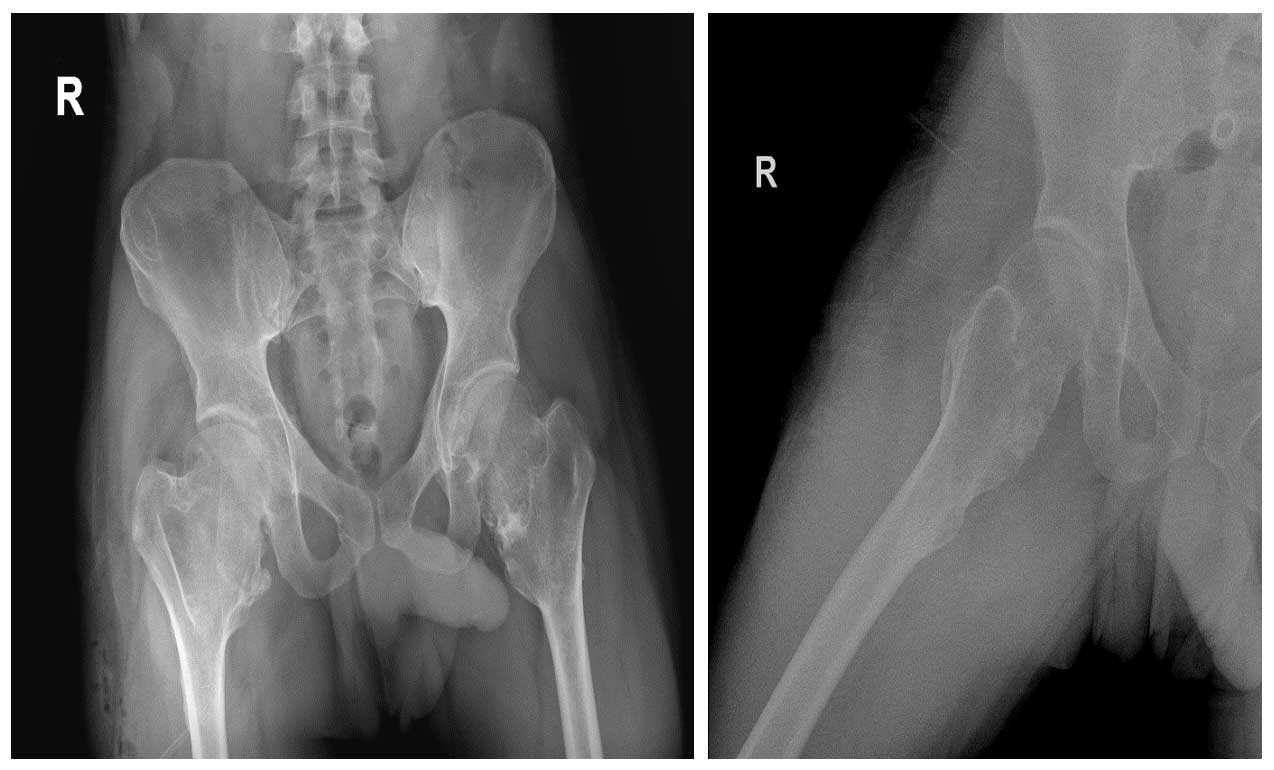

Ameliyat Öncesi: Röntgende kalça ve diz çevresinde yaygın osteokondromlar görülmekte.